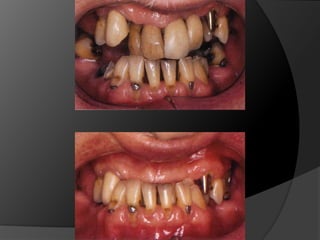

fundamentos de periodoncia en prótesis fijaEl éxito de una prótesis no es medida solamente en el acto de la cementación, sino también a lo largo del tiempo, por estar integrada y en armonía con la estética, tejidos pulpares, tejidos periodontales, músculos y articulación temporomandibular.1

fundamentos de periodoncia en rehabilitaciónEs incuestionable que la salud del periodonto deba ser restablecida antes de cualquier tratamiento restauradorEl paciente es responsable en gran medida del mantenimiento de su salud bucal

fundamentos de periodoncia en prótesis fijaCuando, por la evolución de lesiones de caries, fracturas, o necesidad de ganancia de retención mecánica en pilares muy cortos, el espacio biológico es violado, existe la necesidad de restablecer sus dimensiones, como una forma de recuperar la salud del periodonto y de facilitar los procedimientos protésicos

fundamentos de periodoncia en prótesis fijaCirugía de Alargamiento CoronalExtrusión OrtodónticaTécnica Combinada